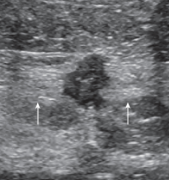

Gynecomastia

Benign hypertrophy of ductal elements in male breast tissue

Causes:

• Puberty

• Disease process

• Medications

Presents:

• Enlarging breast

• Soft palpable mass

Hypoechoic mass